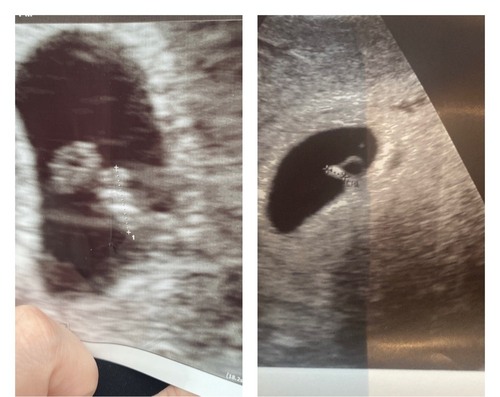

Hier net zo! Vorige week dacht ik 6,5 te zijn en bleek 5,5 te zijn dus schrok ook

En vandaag weer echo gehad en vergeleken met rechts de 1e flink gegroeid dus Verloskundige vertelde mij dat dat prima kon doordat er een late eisprong is geweest .. dus zou echt niet je hoop verliezen hoor als je een mooi hartje hebt zien kloppen